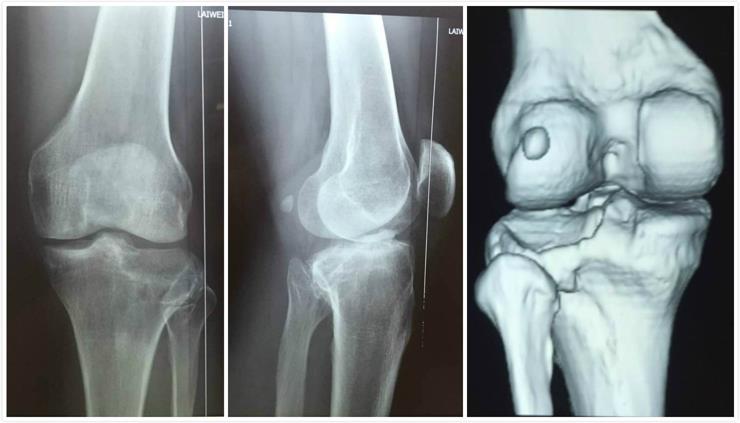

男性病人,43歲,左脛骨平臺后外側塌陷骨折。

術前影像學資料: